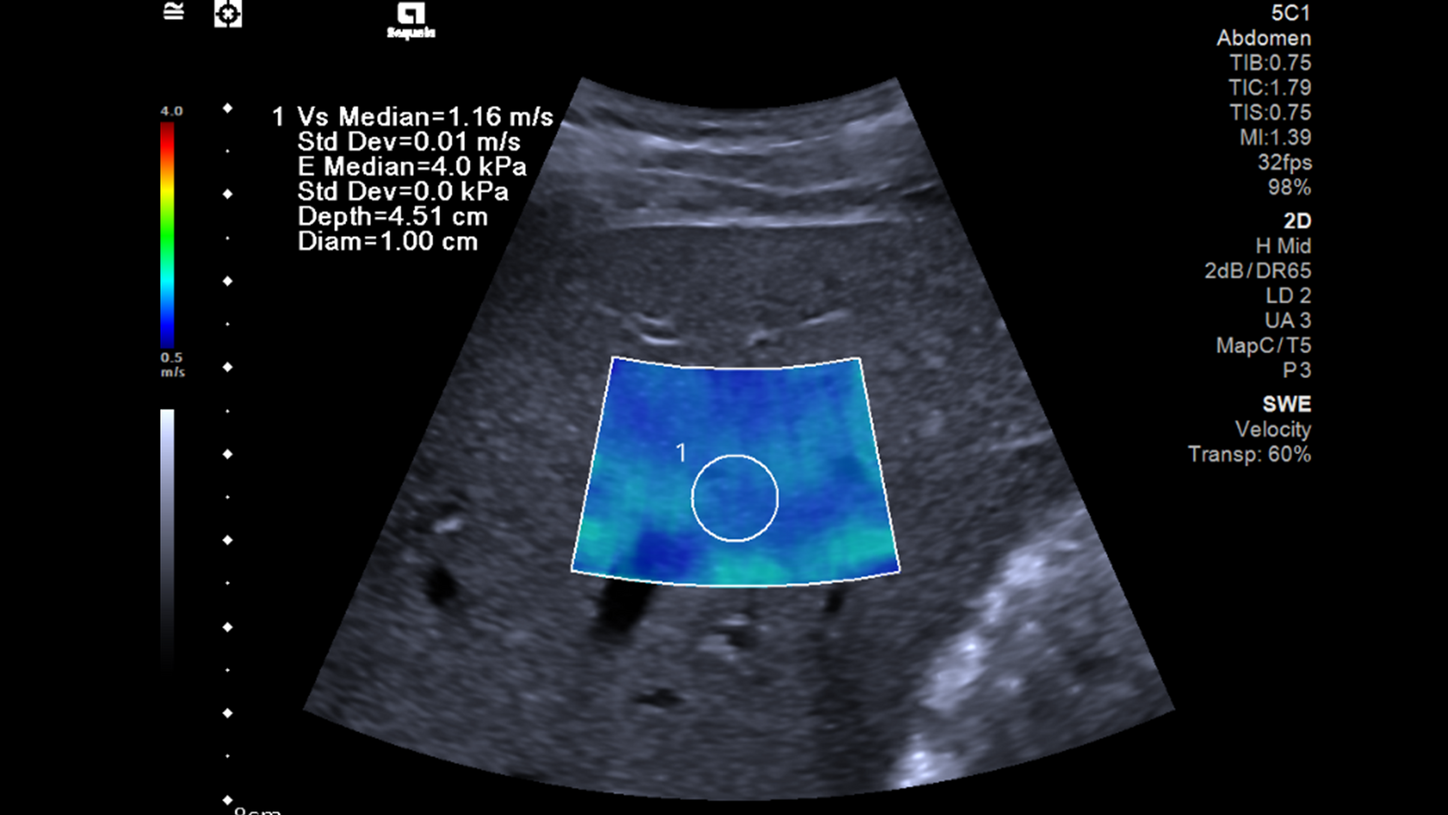

Die Scherwellen-Elastographie

Die Scherwellen-Elastographie misst die Steifigkeit der Leber: Je stärker die Fibrose, desto weniger elastisch das Gewebe – und desto schneller breiten sich Scherwellen aus. Das Ergebnis wird in Meter pro Sekunde (m/s) und in Kilopascal (kPa) angegeben.

2D-Scherwellen-Elastographie